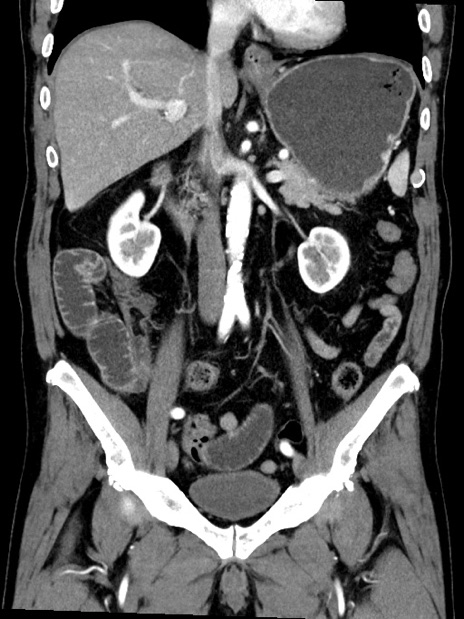

症例35(冠状断像)

【症例】70歳代 男性

【主訴】腹部膨満、嘔吐

【現病歴】昨日より腹部膨満感出現。本日増悪し、仙痛出現。嘔吐あり、受診。

【既往歴】糖尿病、胆摘後

【身体所見】BP 149/80mmHg、HR 74/min、BT 35.9℃、腹部:膨満、軟、圧痛なし。腸雑音減弱あり。上腹部正中切開瘢痕あり。

【データ】WBC 13500、CRP 1.72